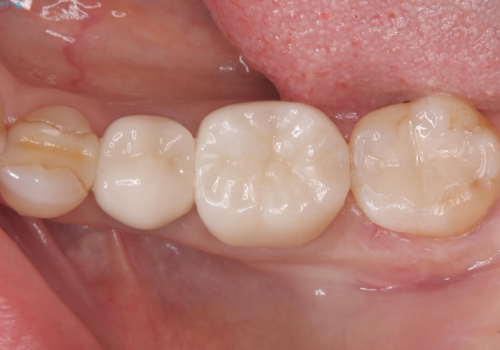

銀歯を白くしたい セラミックインレー

- 銀歯を白くしたいとのことでした。材料の違いを説明し、セラミックインレーでの治療となりました。

接着操作時にラバーダム防湿を行いました。

※左下6番は他のDrで治療を行っています。